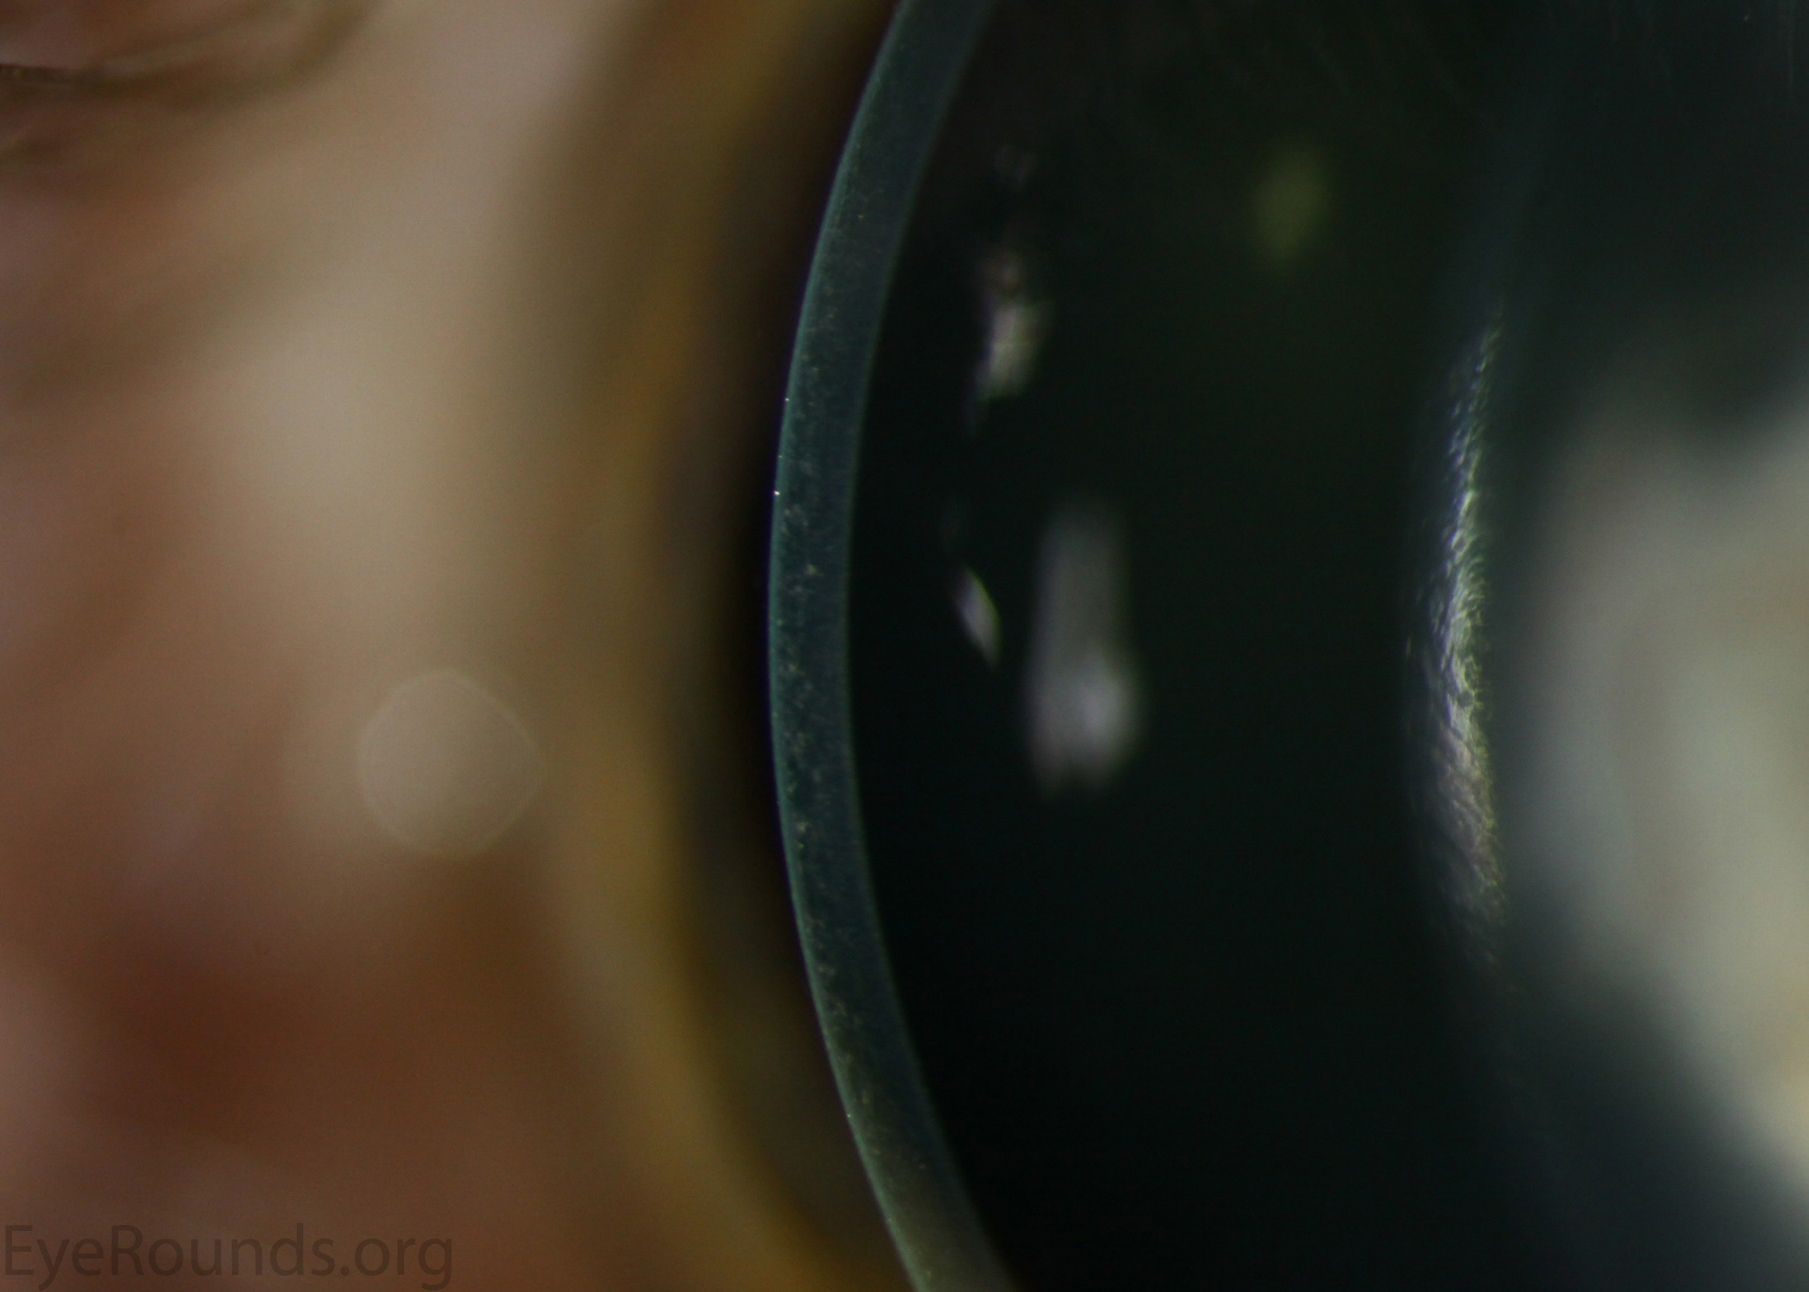

문자그대로 주근깨와 같은 작은 혼탁이 기질에만 존재하는 질환입니다.

작은 혼탁이 상피는 침범하지 않으며, 기질의 전층에 발생합니다.

미세한 회색 얼룩이 양측 각막의 전층에 발생하게되며,

비대칭적이며 종종 단안에만 발생하기도 합니다